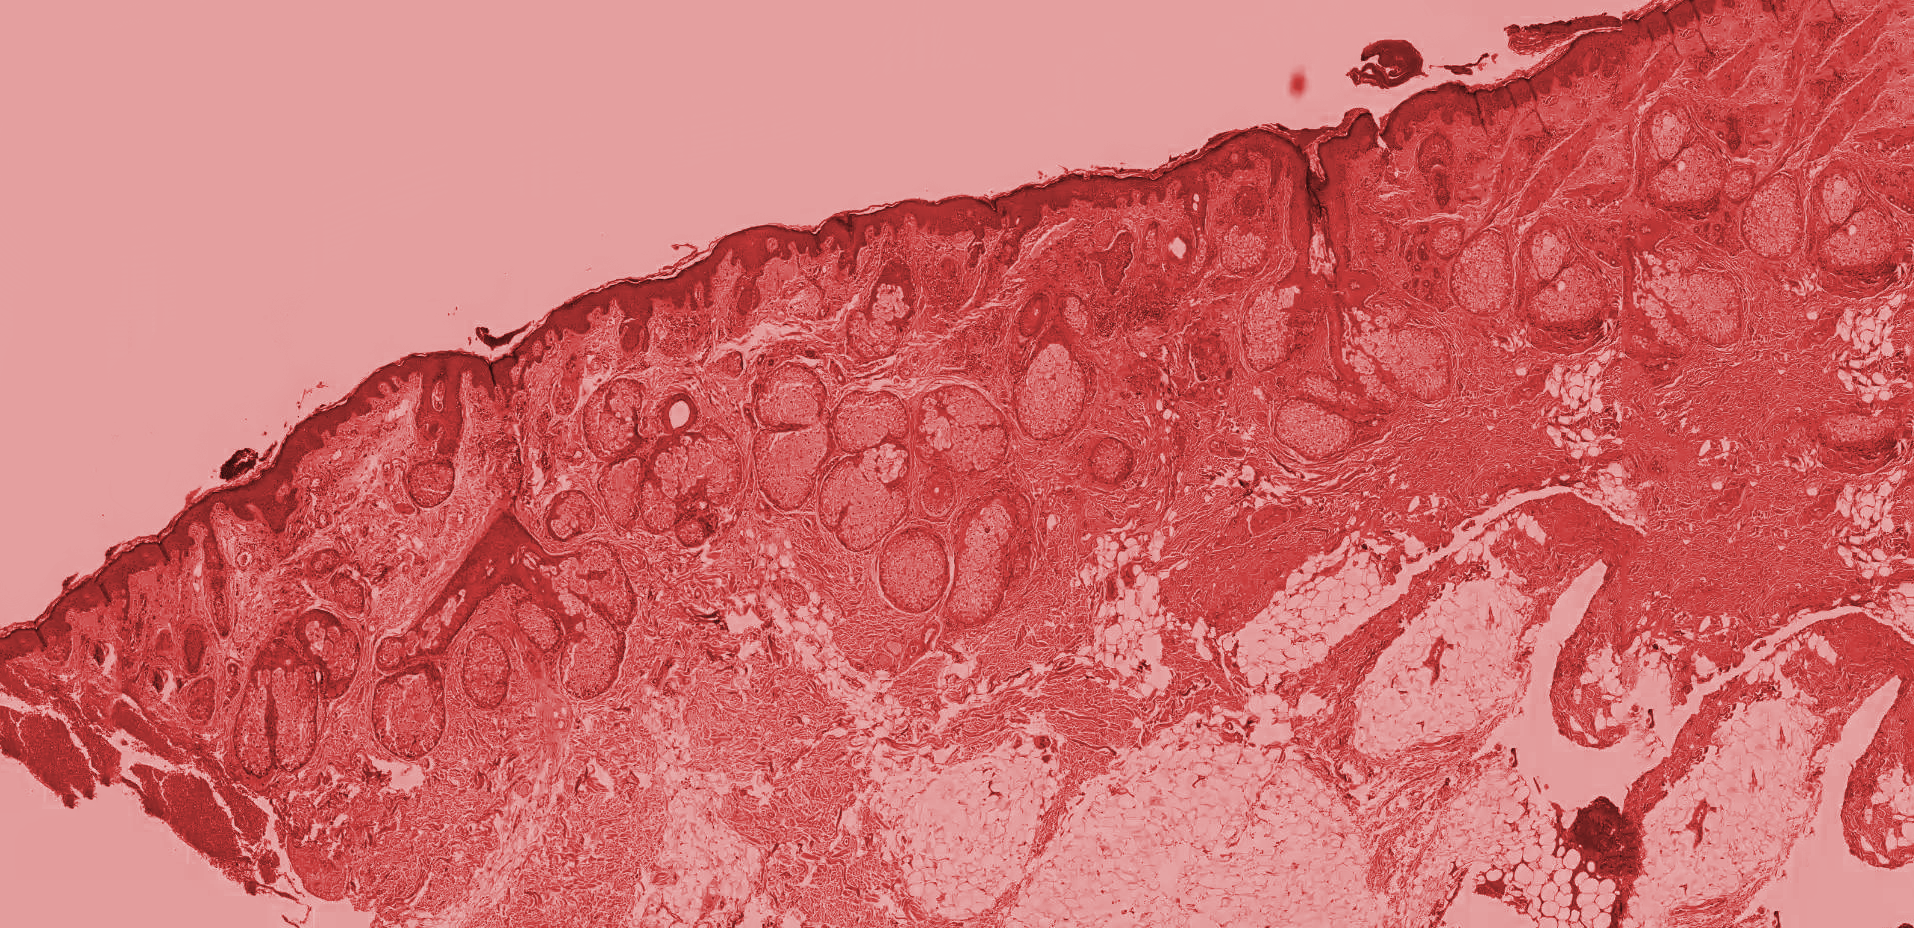

Histología

Se realiza el estudio anátomo-patológico de la biopsia para la detección o descarte de cualquier patología en el tejido.